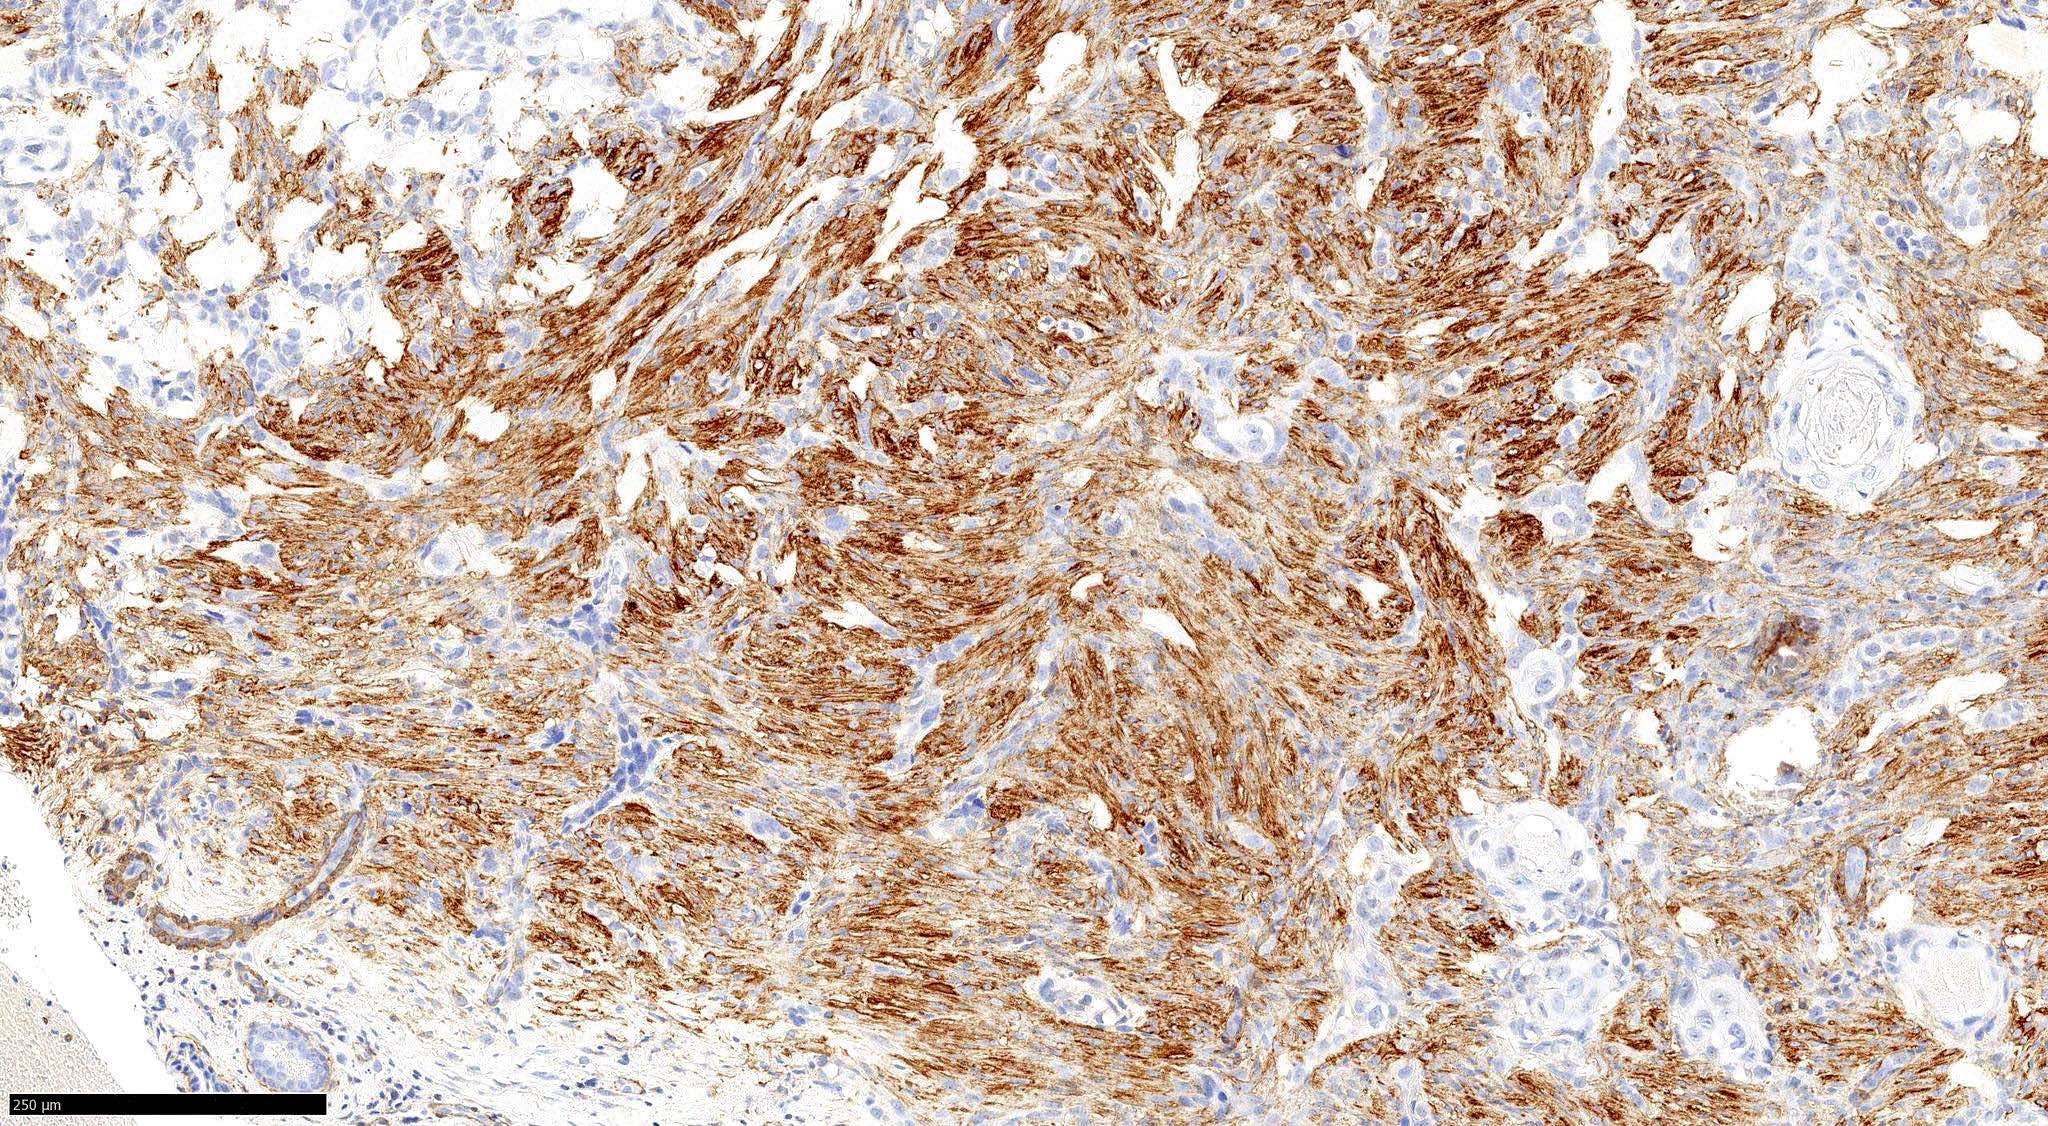

- Morpheaform (sclerosing, morphoeic) BCC

- Thin strands and nests of basaloid cells

- Limited peripheral palisading

- Stroma is dense and sclerotic

- Extensive spread

- Perineural invasion can be seen

Microscopic (histologic) images

Contributed by Antonina Kalmykova, M.D., Phillip H. McKee, M.D., Sate Hamza, M.D., Eduardo Calonje, M.D.,

Wayne Grayson, M.B.Ch.B., Ph.D., James Sampson, M.B.B.S., M.Sc. and Assia Bassarova, M.D., Ph.D.